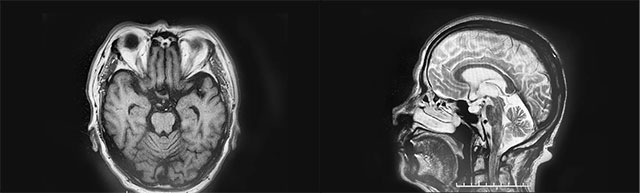

▲ 患者脑体积缩小,脑沟增宽加深,萎缩明显

经磁共振检查,钟老伯有双侧额叶皮层下微腔隙缺血灶,脑萎缩明显。李振并主任介绍,钟老伯具有帕金森病典型的运动症状表现,但帕金森病和帕金森综合征,名字上只是病和综合征之别,却不能简单地混为一谈。